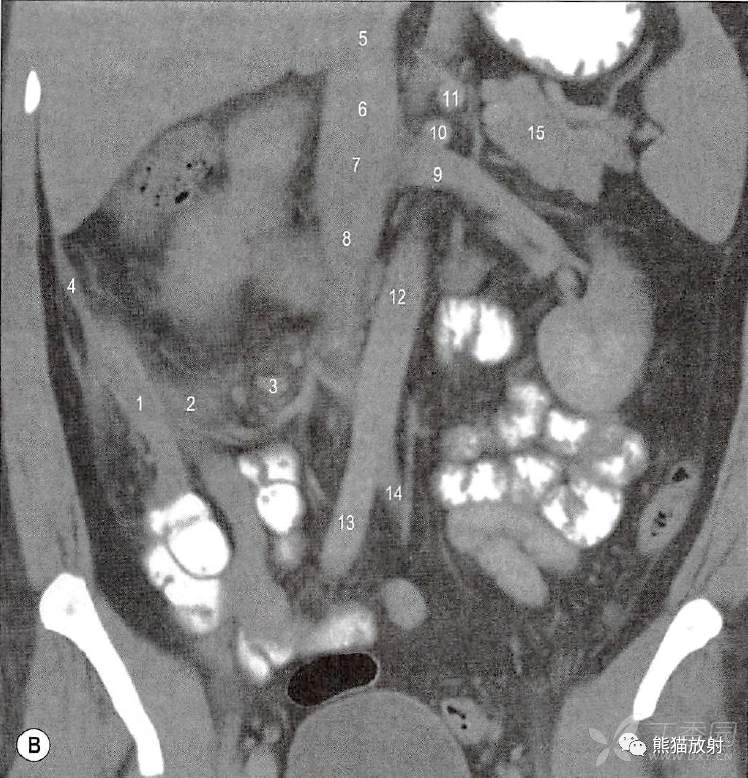

B.经过阑尾的冠状面;1.增厚发炎的盲肠后位阑尾;2.炎性液体和水肿沿右结肠系膜到肠系膜扩展;3.增大的回肠结肠淋巴结;4.右结肠系膜的炎性积液;5.下腔静脉一肝后段;6.下腔静脉一肝下腹膜段;7.下腔静脉一肾段;8.下腔静脉一肾下段;9.左肾静脉;10.肠系膜上动脉;11.腹腔干;12.腹主动脉;13.右髂总动脉;14.左髂总动脉;15.胰尾